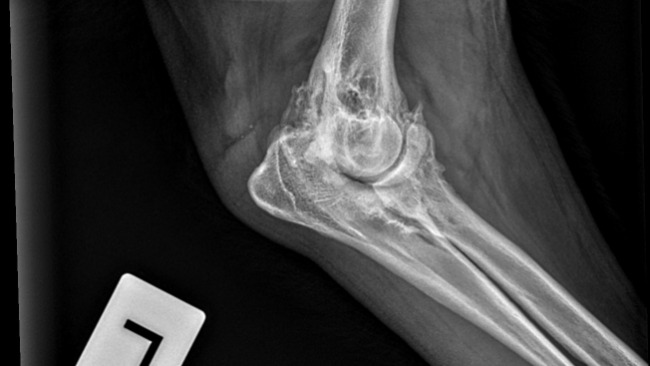

To tak dzielny, wspaniały, kochany zwierzak, że ciężko uwierzyć, że kilka dni temu przeszedł taką ciężką operację.

Nóżka Kokoszka, choć nadal obrzęknięta, dobrze się goi i nasz dzielny psiak stawia na niej swoje wielkie łapeczki.

Sam Kokosz jest teraz taki uśmiechnięty i pogodny, że wiemy, że decyzja o wykonaniu u niego pierwszej z trzech operacji łapek była słuszna i najlepsza.

Fot. Droga chłopaków do równowagi psychicznej. Wizyty w gabinecie lek.wet.